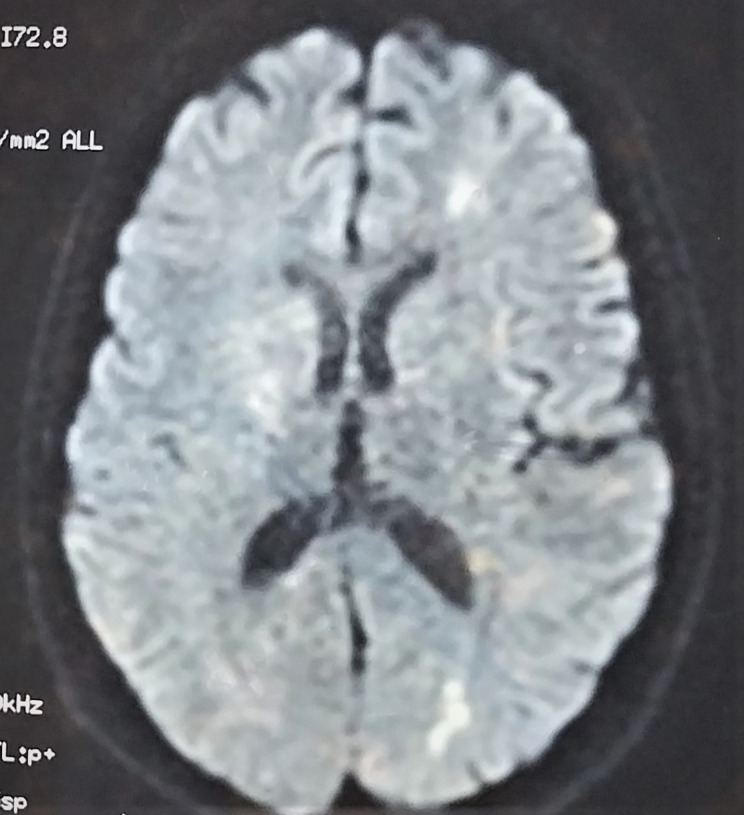

On the seventh day of admission, while her discharge has been planned and discussed with the family, she reported the onset of severe asthenia with dysphagia. Physical examination found fever (body temperature of 40 degrees Celsius), tachycardia (heart rate of 123 beats/min), and multiple mouth ulcers. Thoracic auscultation found normal lung and heart sound. A second neurological evaluation revealed a dysarthria with left hemiparesis, evoking an acute stroke. Another psychiatric examination found a concomitant relapse of psychiatric symptoms. On laboratory tests, she had severe acute kidney failure, proteinuria, high CRP values, and pancytopenia. Infectious investigation was negative. The SARS-CoV-2 PCR with nasopharyngeal swab was negative. Chest X-ray showed bilateral pleural effusion. Immune tests identified the presence of antinuclear antibodies. The anti-ENA (extractable nuclear antigen) antibody screen showed strongly positive anti-SSA, anti-Ro52, anti-SSB, as well as weakly positive anti-nucleosome, and anti-histone antibodies. Brain magnetic resonance imaging (MRI) revealed hyperintense signals in the left fronto-parietal lobes and the cerebellum (Fig. 1). Based on these clinical and laboratory evidence, the patient was diagnosed with SLE according to the 2019 American College of Rheumatology/European League Against Rheumatism (ACR/EULAR) classification criteria [13]. She was then transferred to the internal medicine department and put on Hydroxychloroquine (400 mg daily), prednisone (40 mg daily), Cyclophosphamide (1 g monthly) and risperidone (2 mg daily). Both the SLE and psychotic symptoms improved within one month, and she was discharged. During outpatient follow-up, she was free from neurological and psychiatric symptoms and had good tolerance to treatment.

Fig. 1.

Magnetic resonance imaging (MRI) shows multifocal Hyperintense lesions of the brain (in the left fronto-parietal lobes and the cerebellum) on T2 weighted-images